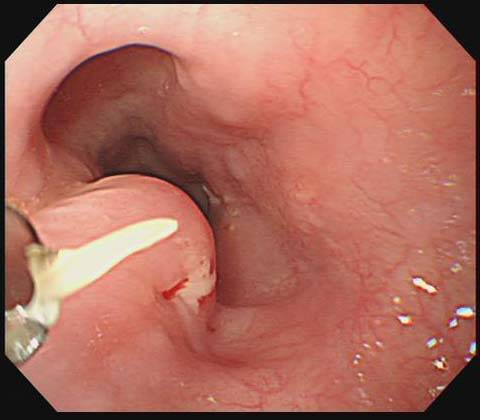

가시가 걸린 뒤 통증이 점점 심해지거나, 침을 삼키기 힘들고 피 맛이 느껴진다면 이미 점막 손상이 시작됐을 가능성이 큽니다. 또 하루 이상 이물감이 계속된다면 가시가 그대로 남아 있을 확률이 높습니다. 아이나 노약자의 경우에는 증상을 정확히 표현하지 못하기 때문에 더 주의가 필요합니다. 병원에서는 내시경이나 전문 도구로 빠르고 안전하게 제거할 수 있으니, 괜히 버티지 마시고 도움을 받으셔야 합니다.